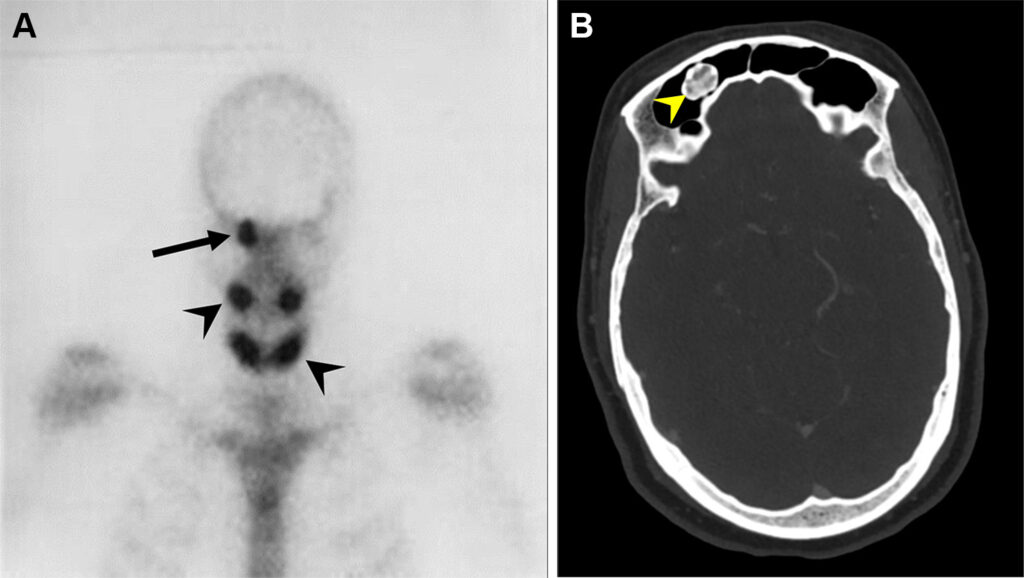

Osteoma del seno frontale in un uomo di 69 anni con sindrome di Gardner.

Lo studio scintigrafico del distretto testa-collo evidenzia aree di intensa ipercaptazione focale (osso frontale destro, ossa mascellari e mandibola). Questo pattern è caratteristico per l’intensa attività osteoblastica tipica degli osteomi.

L’imaging morfologico TC conferma le aree di ipercaptazione come lesioni ossee estremamente dense e ben circoscritte (osteomi), localizzate in questo caso a livello del seno frontale destro.

La sindrome di Gardner è una variante fenotipica della Poliposi Adenomatosa Familiare (FAP). Si caratterizza per la triade clinica: polipi intestinali (ad altissimo rischio di trasformazione maligna), tumori ossei benigni (osteomi, quasi sempre cranio-facciali) e alterazioni dei tessuti molli (tumori desmoidi, cisti epidermiche). La scintigrafia ossea si rivela utile per mappare l’estensione delle manifestazioni scheletriche.